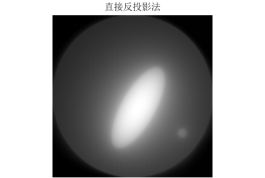

图 9

图 10

图 11

由滤波公式与原来灰度像素矩阵每一列进行卷积,得到了消除边缘失锐的灰度像素矩阵再用原本未滤波的模型进行图形重建运算,程序见附录程序四,结果以及效果如下:

图 14

图 15

图 16